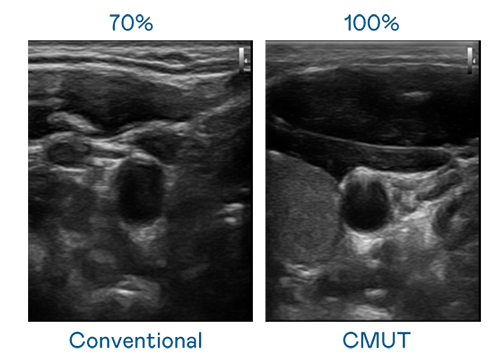

CMUT 技术是一种用电容式微机电元件来产生超音波讯号的技术。与传统 PZT 压电式技术相比,CMUT 频宽增加 30%,更宽频的超音波讯号让影像解析度大幅提升,是实现高影像品质医疗超音波扫描、促进精准医疗发展的关键技术。

超音波影像的解析度高低,首先取决于探头能发出的讯号频宽。天九娱乐 CMUT 可提供高清晰的超音波讯号,提供高频宽、高灵敏度、影像纹理细节更高的超音波影像,协助医护人员缩短影像判读时间及利用精准的医疗影像进行诊断。